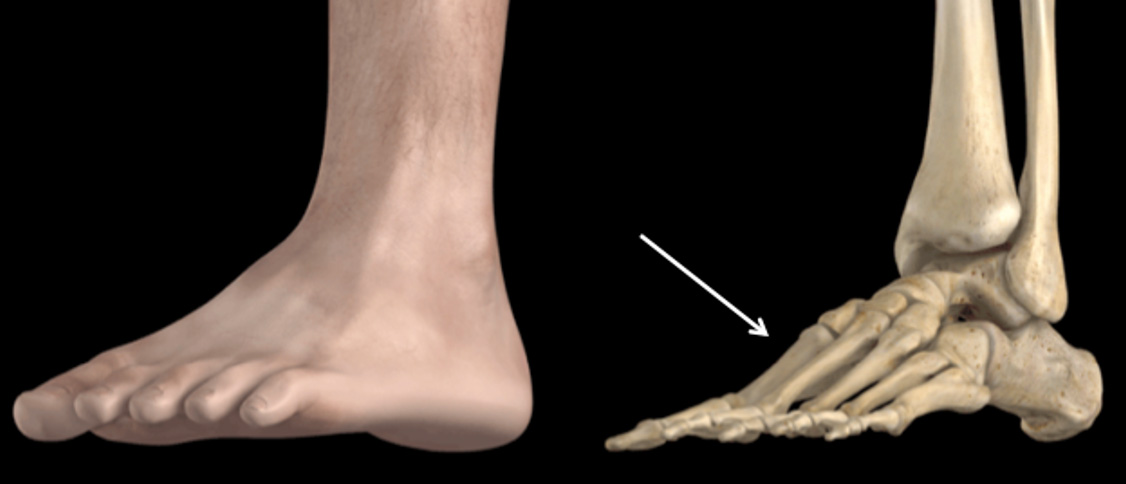

Em termoplástico e tecido aveludado com fecho micro-gancho, uma almofada na zona do primeiro dedo que em conjunto com uma correia de compressão à altura do joanete, mantém os primeiros metatarsos alinhados na posição correcta durante a noite, reduzindo a dor desconfortável e impedindo a sua evolução. Melhor posicionamento da articulação metatarsofalângica do dedo grande do pé. Promove a correção muscular do posicionamento dos dedos.

O tão conhecido Joanete, nome popular do hálux valgo, caracteriza-se por uma saliência na região medial da base do dedo grande (hálux), anatomicamente descrita como articulação metatarsofalângica. O aparecimento deste volume ocorre devido a um desalinhamento ósseo, e não pela formação ou surgimento de osso novo, como muitas pessoas pensam. Além disso, outras deformidades, como dedos em garra, pé plano ou outras alterações, podem estar associadas.